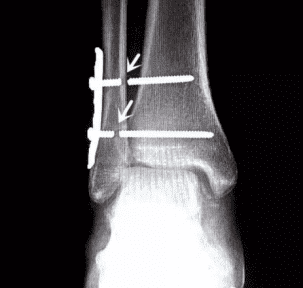

2. Temporary Implants

Temporary implants are used for specific purposes and need to be removed after fulfilling their function. For instance, screws used in ankle fractures are implanted temporarily to ensure proper healing. If not removed in a timely manner, these screws may break or cause complications. Similarly, if internal implants such as screws become loose or cause discomfort, they should be promptly removed.